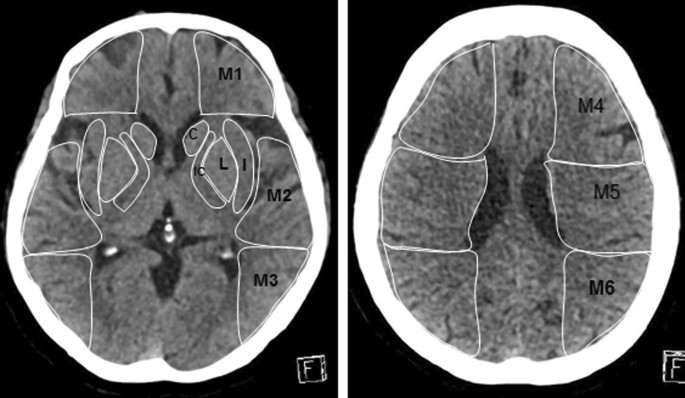

Two radiologists with more than 5 years of neuroimaging diagnosis experience who were blinded to the clinical data measured the NCCT images. Ten separate regions corresponding to the standard middle cerebral artery territory ASPECTS areas were manually outlined. Both investigators defined ROIs limits individually and a consensus read was done to obtain definite ROIs limits that were used for further analysis (Fig. 1). The imaging software (Syngo.via VB20 workstation) calculated the radiological density of each ASPECT region using Hounsfield Units (HU). At least three measurements were carried out in each region and the mean HU values for each ASPECT region were recorded.

Ten ASPECTS regions were outlined on the NCCT images. HU ratio in ten ASPPECTS regions, C: 41.75/41.81, M1: 39.99/38.31, M4: 39.41/39.82, L: 41.82/41.29, M2: 42.11/44.54, M5: 37.26/37.72, IC: 31.67/34.03, M3: 41.19/38.85, M6: 38.95/39.04, I: 35.17/40.82. HU difference in ten ASPPECTS regions, C: |41.75–41.81|, M1: |39.99–38.31|, M4: |39.41–39.82|, L: |41.82–41.29|, M2: |42.11–44.54|, M5: |37.26–37.72|, IC: |31.67–34.03|, M3: |41.19–38.85|, M6: |38.95–39.04|, I: |35.17–40.82|

The HU value of 10 ASPECTS area of the infarct side cerebral hemisphere was divided by the HU value of the corresponding ASPECTS area of the healthy side cerebral hemisphere to obtain 10 HU ratios and the HU ratio of each patient was obtained by adding the ratio of each area. The HU value of 10 ASPECTS area in the infarcted side cerebral hemisphere was subtracted from the HU value of the corresponding ASPECTS area of the healthy hemisphere to obtain 10 HU differences and the HU difference of each patient was obtained by adding the difference of each area.